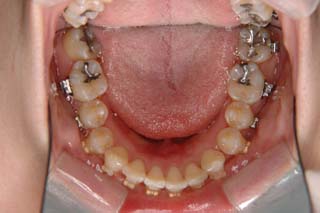

診断名:叢生を伴う上顎前突

使用した主な装置名:TPB、マルチブラケット装置、歯科矯正用アンカースクリュー

抜歯/非抜歯および抜歯部位:抜歯(上顎左右第一小臼歯)

治療期間:動的処置2年6か月、経過観察3年

かなり強い上顎前突を示します。その他の問題はなさそうですが、小臼歯抜歯だけでは上顎前突に対応しきれそうにありません。上顎大臼歯に最大限の固定が必要と考えられましたので、上顎左右の臼歯部に計2本の歯科矯正用アンカースクリューの植立を検討してみました。